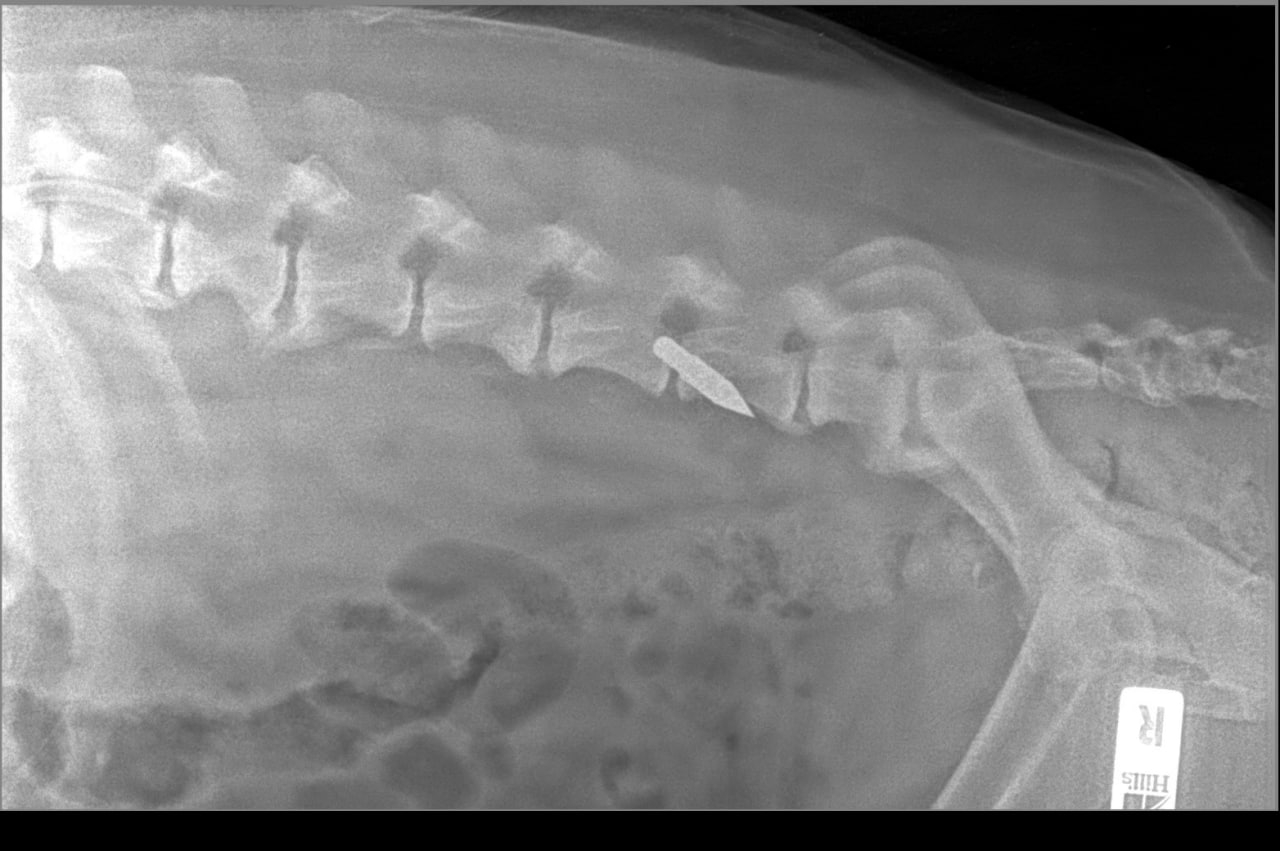

Напомним, раненого пса нашли поздно вечером 22 февраля в районе ММС в луже крови. Животное было ослаблено и переохлаждено. И хотя жизненно важные органы не были задеты и помощь подоспела, 10-летний пес не справился.

Фото: страница фонда "Потеряшки" в ВК